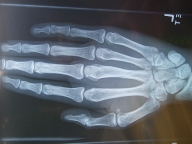

骨折も脱臼の経験すらなかったので、しかも指も動くしむちゃくちゃ痛くもないので、まさか骨折しているとは思わなかった.

部位は根幹部. こんな場所.

でも完全に折れてるわけではなくて大きなひびが入ったかんじ. 中指.

どうも脱臼ぽくないと思ってたし、間接部じゃなくて手全体が腫れてた感じなので、「そうか折れてたのか」と納得.